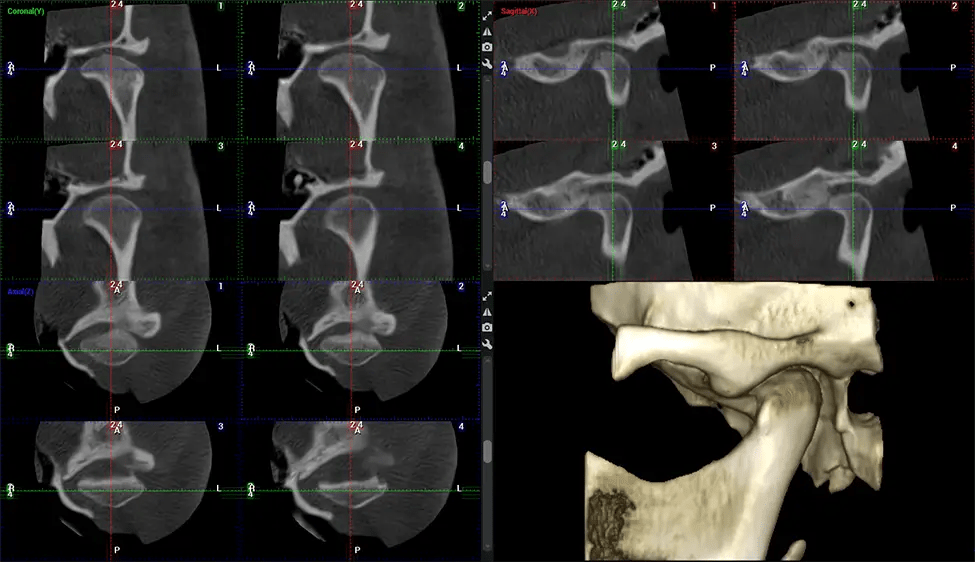

Esta exploración 3D, llamada tomografía computarizada de haz cónico, le brinda a su dentista una imagen más completa de su anatomía bucal y sus procesos patológicos que una radiografía tradicional. A diferencia de las radiografías convencionales, que capturan una imagen 2D de la boca desde varios ángulos, una exploración 3D toma varias radiografías digitales para una imagen. Proporciona una vista completa de la mandíbula, los dientes, los nervios y los tejidos blandos. Esta vista mejorada permite a los dentistas detectar problemas menores que no son visibles en las exploraciones 2D tradicionales, como muelas del juicio impactadas o fracturas óseas en la cavidad sinusal.

Otro beneficio importante es que las imágenes 3D proporcionan imágenes más precisas de la estructura ósea. Estas imágenes son más detalladas y le brindan un diagnóstico más preciso. Un diagnóstico preciso significa un mejor tratamiento para usted.

Después del proceso de escaneo, las imágenes de rayos X capturadas son procesadas por el software CBCT, que aplica algoritmos para reconstruir una imagen 3D detallada del área escaneada. El software recopila estas imágenes de rayos X individuales y crea una representación digital en 3D de la anatomía del paciente. El dentista o el radiólogo pueden ver y analizar la imagen CBCT 3D reconstruida. Esta imagen se puede manipular, rotar y acercar o alejar para examinar estructuras específicas y evaluar la condición del paciente.